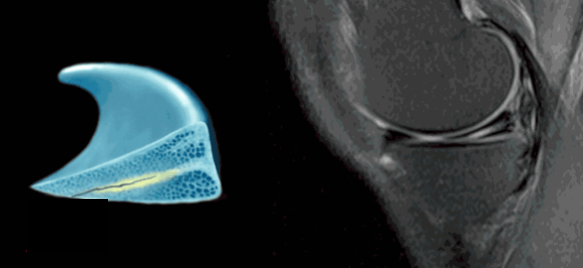

半月板在膝关节MRI上的图像

半月板损伤在膝关节MRI上的示例

半月板损伤的三类信号